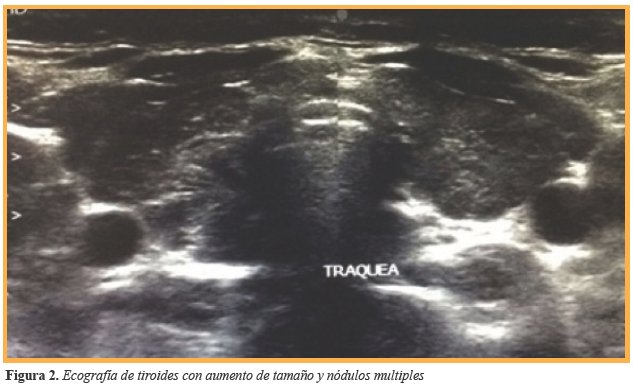

Ecográficamente se caracteriza por hipoecogenicidad y heterogenicidad del parénquima glandular, variable de acuerdo con la fase o etapa evolutiva de la patología tiroidea; por esta razón, el centellograma tiroideo y el estudio de captación de Yodo no son herramientas diagnósticas útiles. Las pruebas de función tiroidea evidencian deficiencia de T4 total y libre junto con una TSH elevada. La presencia de anticuerpos anti Tiroglobulina y anti Tiroperoxidasa son fundamentales para corroborar el diagnóstico. Asociado a estos, la presencia de bocio difuso de consistencia aumentada sin otra enfermedad tiroidea conocida e infiltración linfocitaria confirmada por estudio citológico mediante Punción con Aguja Fina (PAF)2. Es sugestivo de TH la presencia de datos clínicos de hipotiroidismo asociados a una respuesta autoinmune tiroidea manifestada por elevación de anticuerpos antiperoxidasa o un resultado de ecografía tiroidea acorde con el diagnóstico de tiroiditis crónica2.

Debido a antecedentes y sintomatología referido por la paciente, se inició protocolo de estudio. El reporte de bioquímicos fue glucosa 90 mg/dl, Hb1Ac 5,2%, insulina 16,5 μUl/ml, HOMA-IR 3,66; triglicéridos 90 mg/dl, colesterol total 152 mg/dl, HDL 38 mg/dl, LDL 96 mg/dl, ALT 21 u/1, sin reunir criterios para Diabetes Mellitus ni para Síndrome Metabólico, por lo que se decidió completar el abordaje inicial realizando pruebas de función tiroidea ante la sintomatología digestiva y ginecológica referida por la paciente, obteniendo como resultados los mencionados en la (Tabla 1). Ante la detección de hipotiroidismo primario y debido a que la principal etiología es autoinmune, se complementó protocolo de abordaje con realización de anticuerpos, destacando la elevación de: anticuerpos antitiroglobulina 0,90 Ul/ml, anticuerpos antiperoxidasa 359,40 Ul/ml, ANA 1:100, concluyendo diagnóstico de Tiroiditis de Hashimoto. Debido al hallazgo de bocio, se realizó ultrasonido de cuello con reporte de incremento en el tamaño de los lóbulos tiroideos a expensas de lóbulo derecho con nodulos tiroideos sin calcificación ni vascularidad incrementada (Figura 2) la paciente cursaba con irregularidad menstrual por lo que se solicitó ultrasonido pélvico el cual fue reportado sin alteración (Figura 3).

Aunque se sabe que la tiroiditis de Hashimoto en niños y adolescentes puede entrar en remisión a largo plazo, y que el tratamiento con Tiroxina (T4) puede no ser necesario, es difícil cuantificar los cambios en el grado de destrucción autoinmune de la tiroides. Al igual que el caso presentado, existen reportes similares de Tiroiditis de Hashimoto en adolescentes femeninos en los cuales tras iniciar el manejo sustitutivo con levotiroxina es factible lograr cambios funcionales y anatómicos evaluados por las mediciones de hormonas y la ecografía7 aunque según Radetti et al, hasta el momento es complejo determinar si los pacientes con obesidad y alteraciones en la función tiroidea progresarán o no a alguna enfermedad tiroidea crónica, por lo que se recomienda insistir en el seguimiento..